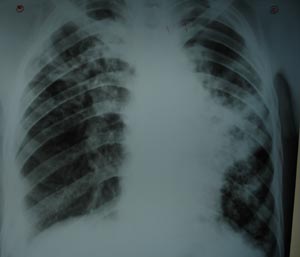

Left mid zone opacity

Left mid zone reveals an opacity, which appears to be arising from the left bronchus, suggestive of ? bronchogenic carcinoma unless & until ruled out. Also there is an invovment of right upper segment & right hilum.